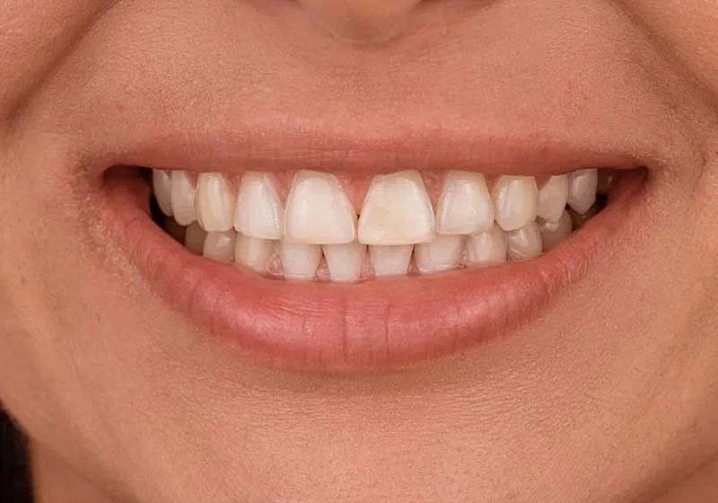

Существует 2 вида реставраций: с нанесением керамической массой и методом раскрашивания. Второй вариант в нашей клинике применяется чаще всего. Этот метод дает высокий эстетический результат. Первый вариант с нанесением керамики имеет недостаток, керамика может со временем скалываться, что вызывает неудобство в использовании протеза.